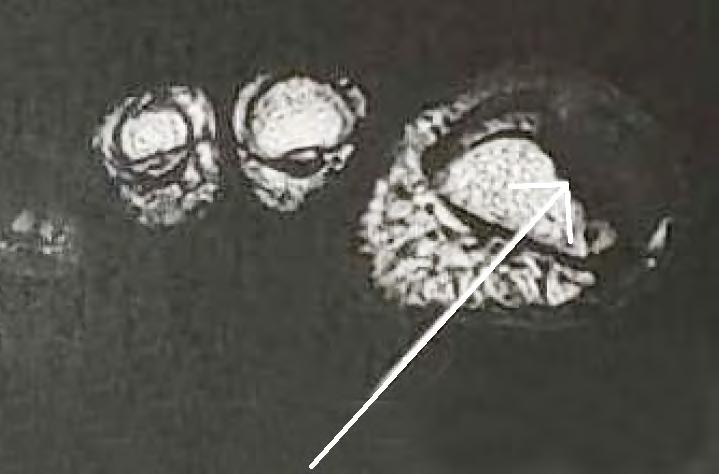

Onicomatricoma - sempre um desafio diagnóstico

Soraya Neves Marques Barbosa dos Santos, Sílvia Iovine Kobata, Isabela Boechat Morato, Natália de Paiva Sobreira